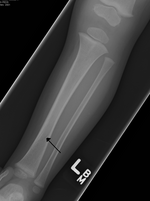

Maisonneuve fracture Jules Germain François Maisonneuve spiral fracture of proximal fibula external rotation of ankle Maisonneuve fracture Archived 2020-09-22 at the Wayback Machine at Wheeless' Textbook of Orthopaedics online Maisonneuve fracture Fibula.JPG